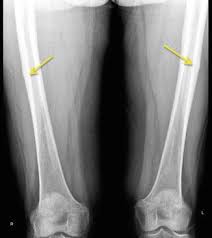

Stress injuries can be found in the shin bone foot heel hip and lower back. Eat more calcium- and vitamin D-rich foods or take supplements. If the pain is manageable and you can walk without too much discomfort start with at-home treatment.

Stress Fractures Causes Symptoms Treatment Recovery Complications